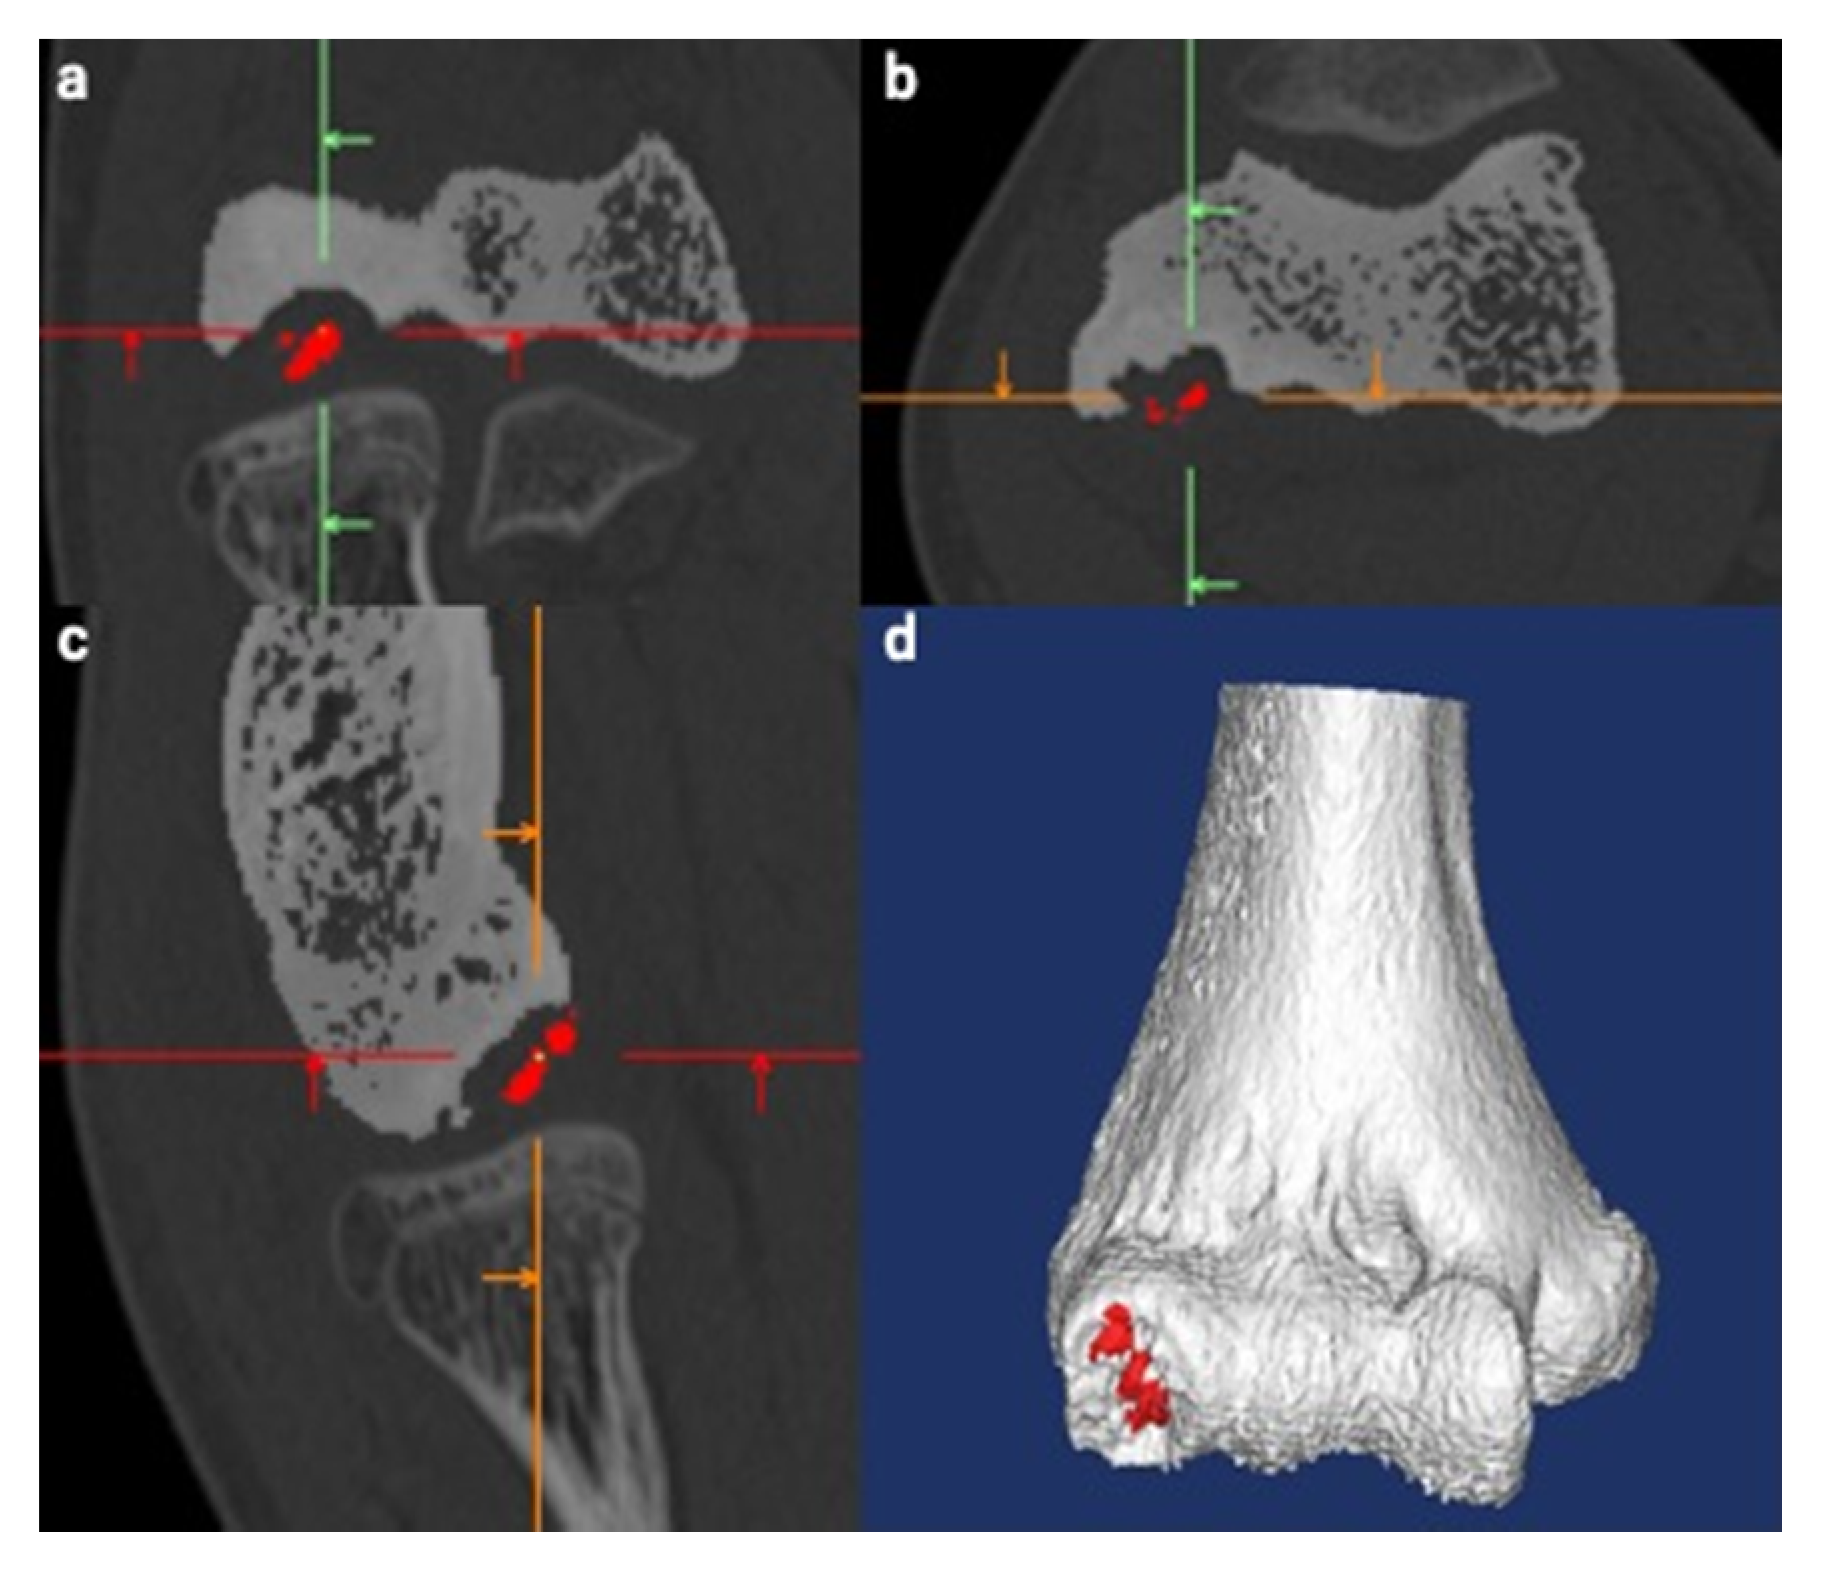

2.3. Creation of 3D Models

2.4. Fusion of Created 3D Models

2.5. Lesion Evaluation Using MCFIs